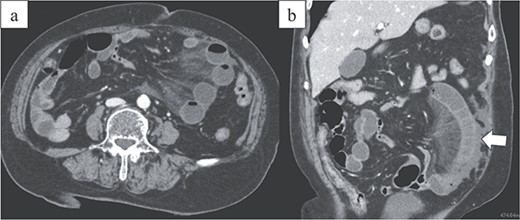

An 86-year-old woman with no prior abdominal surgeries was admitted to our hospital complaining of constant abdominal pain with an acute onset of 8 hr duration. The physical examination revealed tenderness of the lower abdomen. The laboratory test results were unremarkable, except for elevated lactate (3.0 mmol/l) and leukocyte counts (14 400/μl). Contrast-enhanced computed tomography (CT) revealed a closed-loop obstruction of the hypo-enhancing small bowel in the left lower abdominal quadrant, which suggested a strangulated bowel obstruction (Fig. 1). The duodenum did not form a horizontal limb and ran caudally to the jejunum (Fig. 2). The duodenojejunal flexure was abnormally located in the right upper abdominal quadrant, which suggested an intestinal malrotation. Sac-like capsulated small-bowel loops were barely visible.

Images from enhanced CT. (a) Arterial-phase axial CT shows a hypo-enhancing small bowel in the left lower abdominal quadrant. (b) Arterial-phase coronal CT coronal enhanced CT shows a closed-loop obstruction of the hypo-enhancing small bowel (arrow).